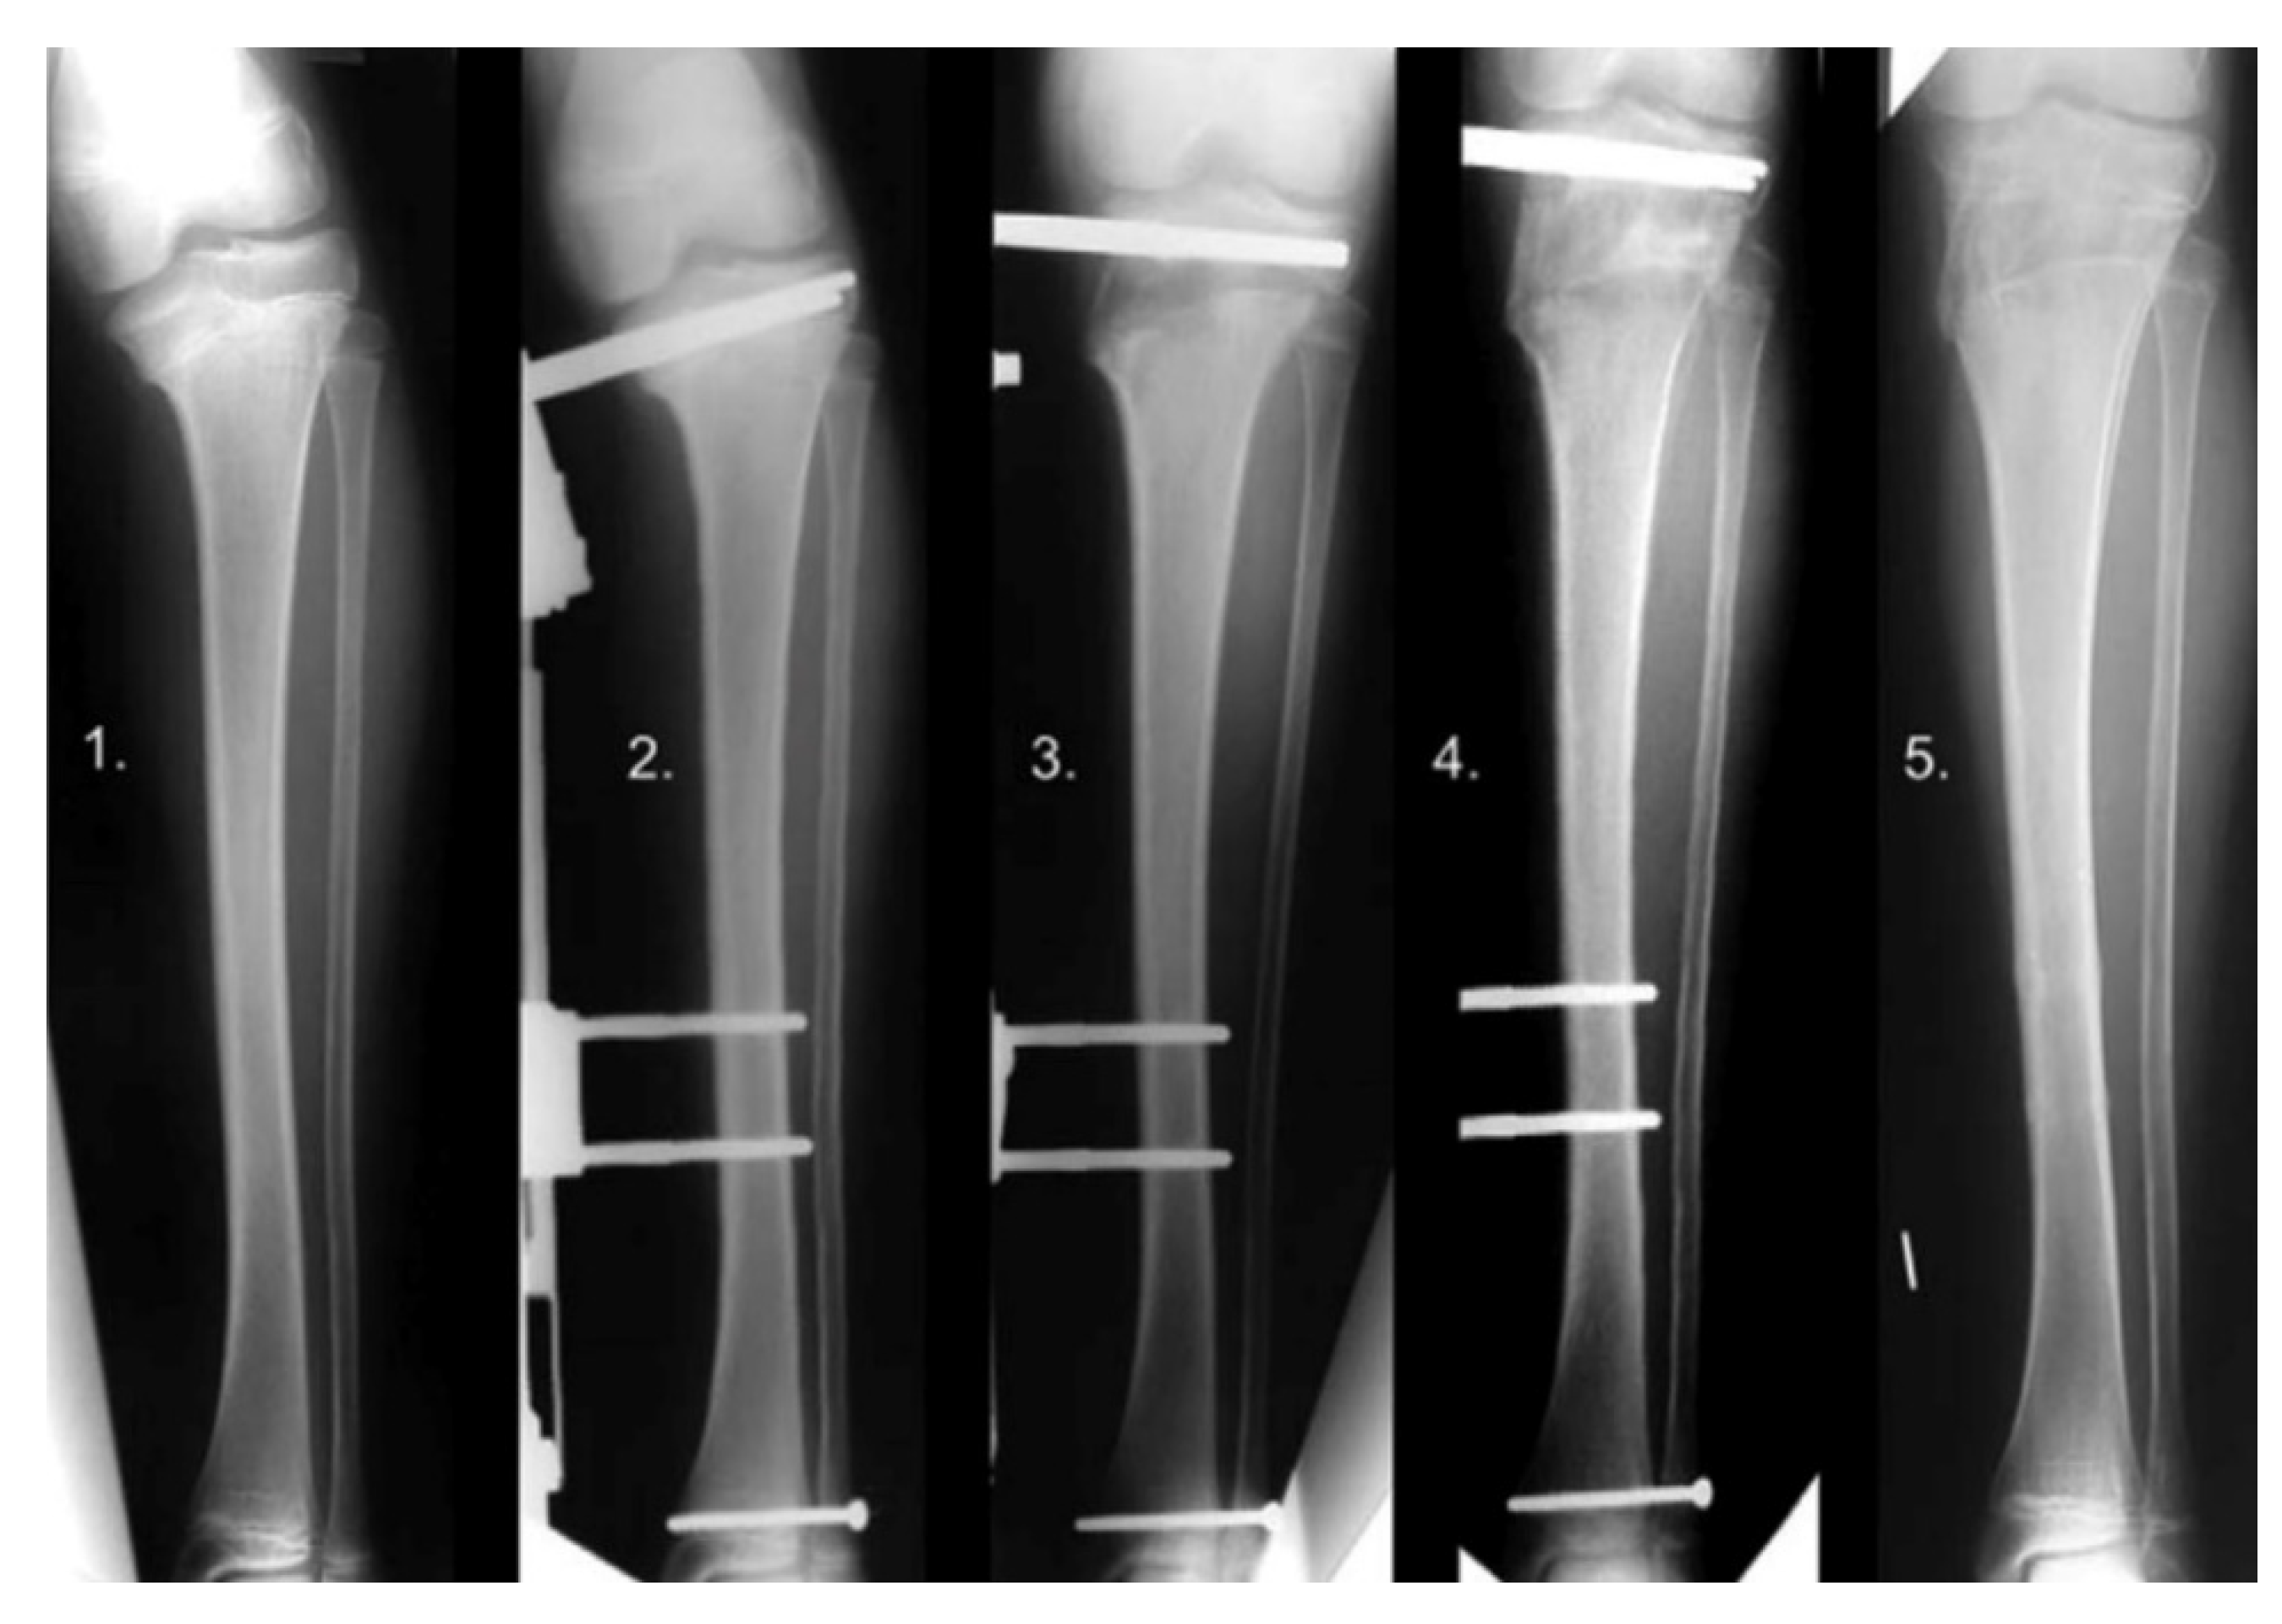

12. Physeal Arrest Resection

13. Osteotomies with Acute Correction